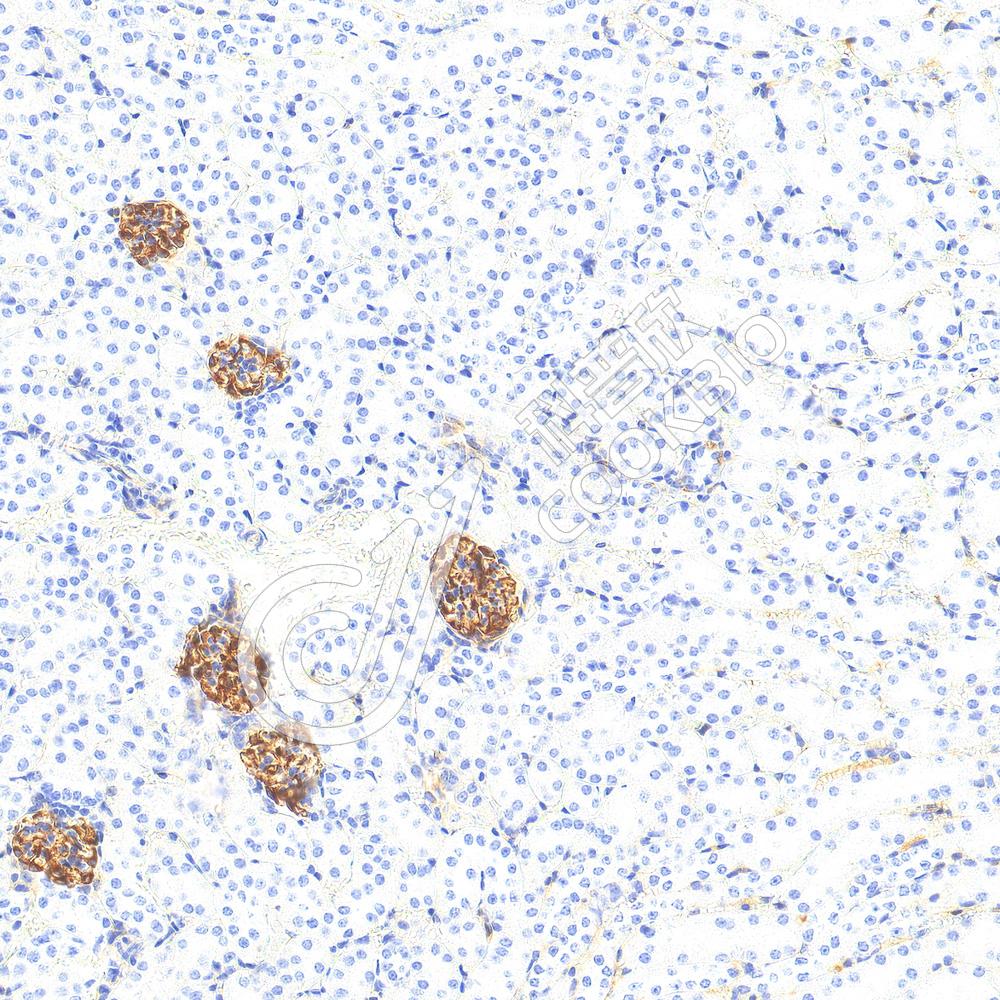

IF检测Phospho-Tau(S202/T205)蛋白(货号 K5450180)(红色).

样品: 人结肠, 4%多聚甲醛 (货号KSG1101) 固定12-24小时.

抗原修复: 柠檬酸抗原修复液(干粉, pH 6.0) (KSG1201), 高压锅均匀喷气计时2分钟.

封闭: 3% BSA(货号KSGC305010)的PBS溶液, 室温孵育30分钟.

—抗: 1: 300稀释, 4℃ 孵育过夜.

二抗: Cy3标记山羊抗兔IgG (H+L) (货号KB63909), 1: 300稀释, 室温孵育1小时.